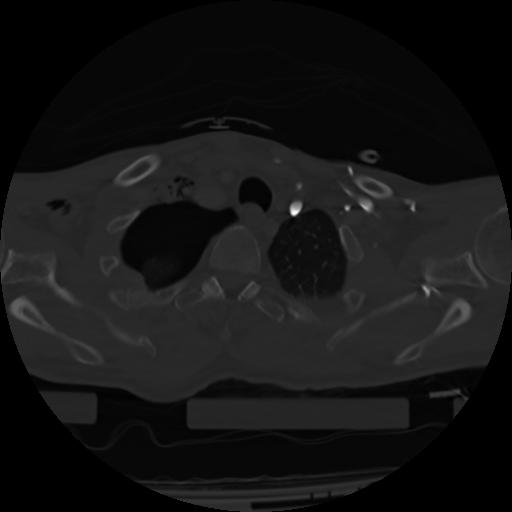

21 ANGIO,CE,Axial,3.0,ANGIO,,